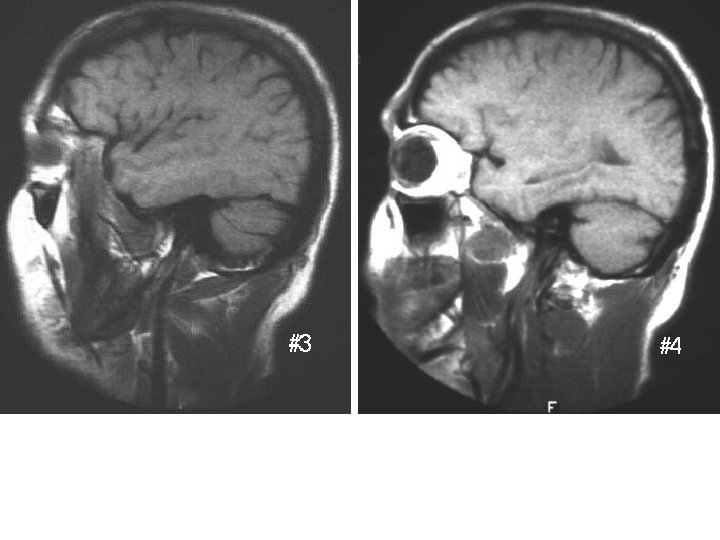

This one